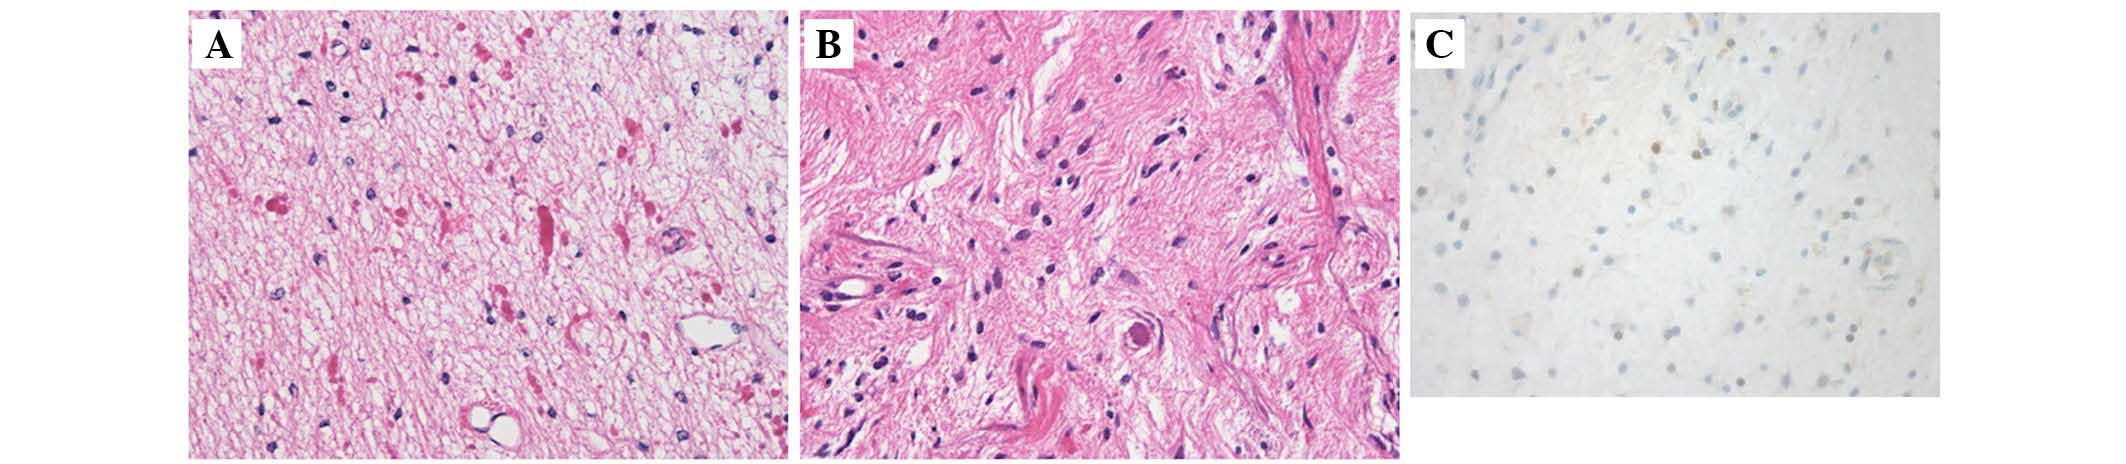

A case of pilocytic astrocytoma requiring tumor resection during pregnancy

Low-grade glioma (LGG) is often encountered in relatively young individuals, including women of childbearing age. Notably, case series describing pregnant women with LGG have been reported in the literature. The present study reported a case of pilocytic astrocytoma (PA) requiring tumor resection during pregnancy. The patient had a history of γ‑knife radiotherapy for a brainstem tumor 17 years previously. The histological diagnosis was unclear. The tumor had remained stable following radiosurgery for 17 years, including during her first pregnancy. However, rapid tumor growth around the fourth ventricle occurred at week 25 of her second pregnancy. Therefore, an urgent tumor resection was performed despite the pregnancy. Partial resection was performed since the tumor had infiltrated the brainstem. The histological diagnosis was PA. The residual tumor volume decreased gradually following the delivery. Immunostaining of the tumor for the expression of progesterone receptor revealed focal staining. It is possible that reproductive factors, including specific hormonal changes during pregnancy, affected the tumor growth. The present study described this rare case of PA, which exhibited rapid growth and required urgent surgery during pregnancy.

Figure 1

Figure 2

Figure 3

Figure 4